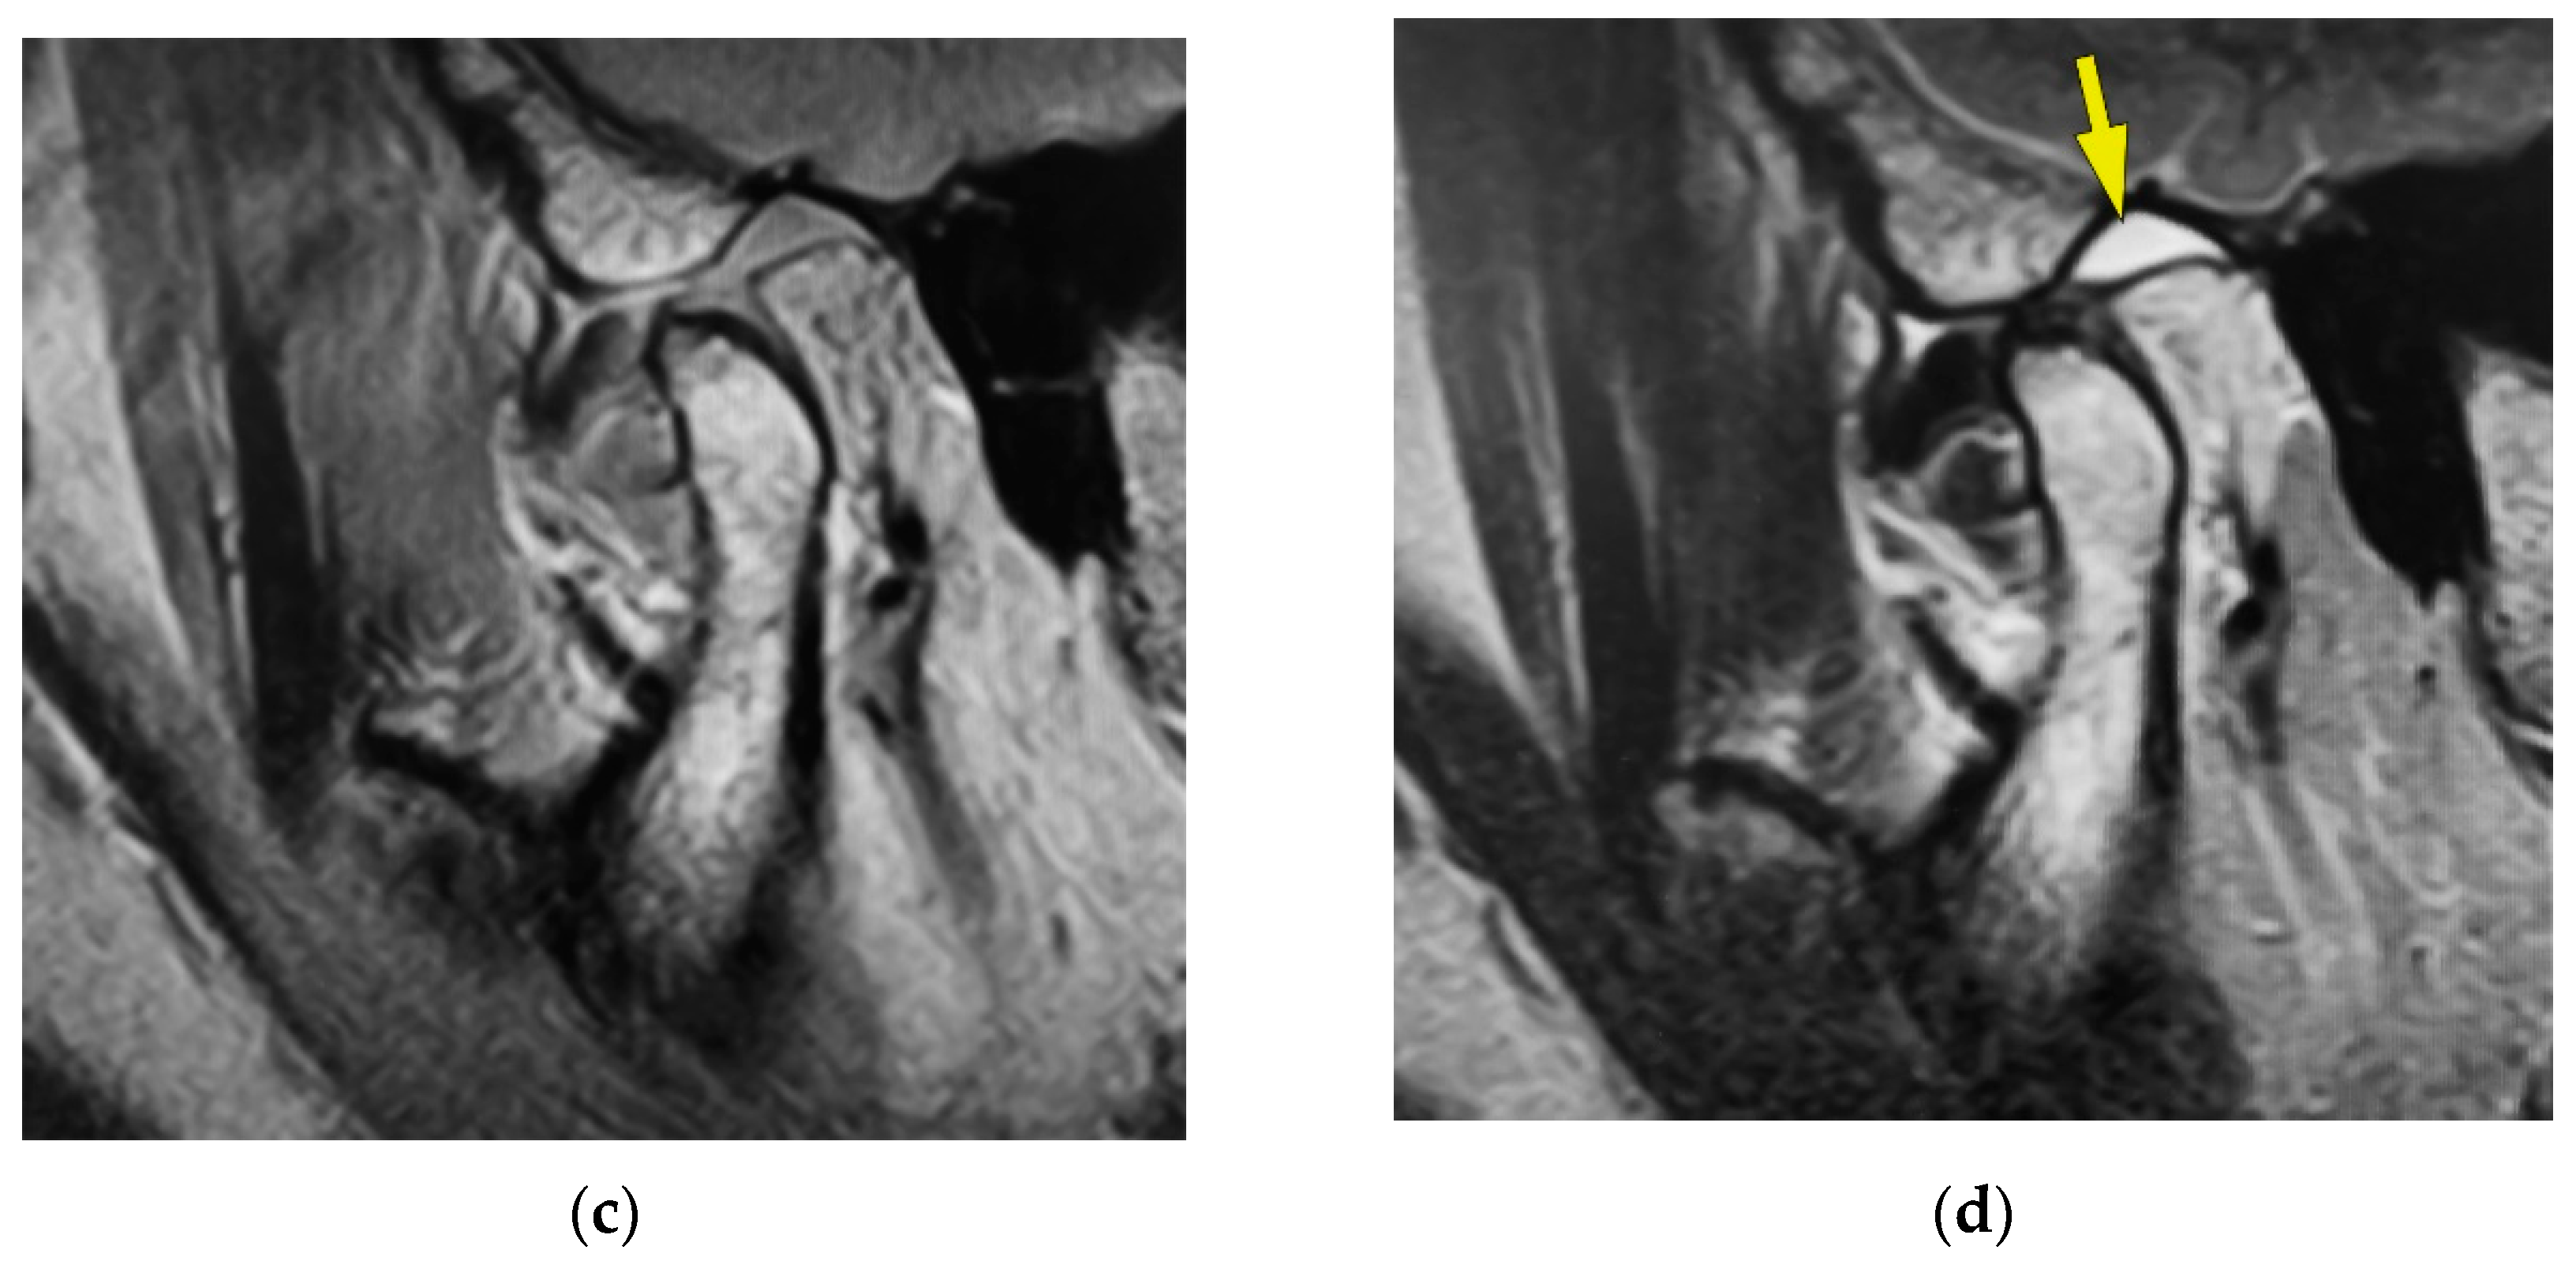

Examination for the Factors Involving to Joint Effusion in Patients with Temporomandibular Disorders Using Magnetic Resonance Imaging